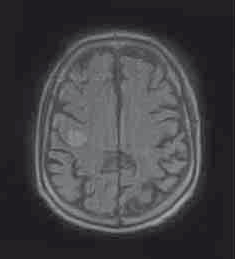

80岁男性,由于口齿不清和左侧面部下垂就诊。MRI检查前两图。初步诊断为急性脑梗死,患者接受阿司匹林和氯吡格雷治疗2天后出院。 16天后,患者由于左上肢麻木无力2天再次就诊。 既往史:高血压、高血脂,慢性阻塞性肺疾病,冠心病支架放置术后7年,右侧脓胸剥脱术8年。曾吸烟,无饮酒或违禁药物使用史。 家庭史:无神经系统疾病遗传史,亲属有心肌梗死及结肠癌患者。 体格检查:一般体格检查未见显著异常。神经查体显示患者言语流畅,但为构音障碍性言语,此外还存在吞咽困难、显著左侧面部下垂,多步骤命令执行困难。左侧上肢肌力减弱(近端3/5,远端4/5),精细动作协调性障碍,边距不良,轮替运动障碍。 辅助检查:患者的血象和炎症标记物均在正常范围内。颈动脉超声检查未见显著异常。MRI扫描见第三图。